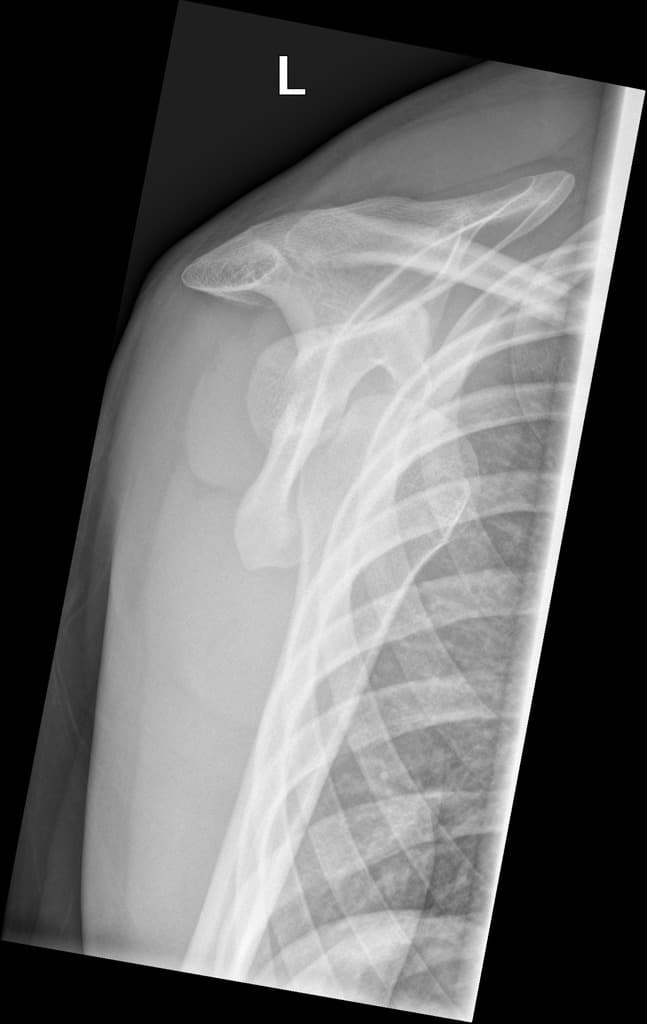

Ca bệnhTrật khớp vai tái phát

Trật khớp vai tái phát

Tiền sử trật khớp tái hồi

Trật khớp vai tái hồi

Trật khớp tái hồi thường gặp ở khớp vai, thường là kết quả của một chấn thương ban đầu làm tổn thương các cấu trúc ổn định như sụn viền ổ chảo hoặc bao khớp, dẫn đến tình trạng mất vững mạn tính.